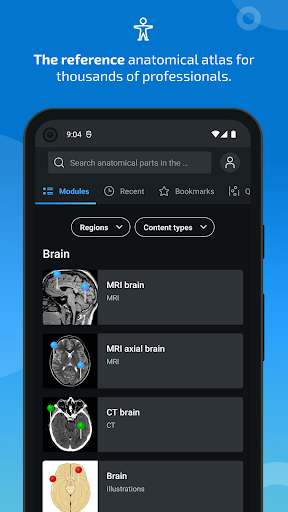

جديد: يمكنك الآن تصفية الوحدات حسب المنطقة أو نوع المحتوى حتى تتمكن من العثور على الوحدة التي تبحث عنها بشكل أسرع.